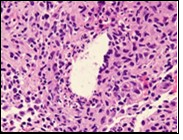

Figure 2.Granulomatous mastitis with articulated epitheloid cell granuloma, lymphocytic, plasma cell and neutrophilic infiltration10.

Granulomatous mastitis with articulated epitheloid cell granuloma, lymphocytic, plasma cell and                   neutrophilic infiltration10.

Core needle biopsy of idiopathic granulomatous mastitis enunciates multiple aggregates of non- caseating epitheloid cell granulomas within and encompassing breast lobules, constituted of epitheloid histiocytes, lymphocytes, neutrophils and multinucleated giant cells. Granulomatous inflammation is predominantly lobulo-centric. The inflammation is preponderantly composed of lymphocytes, plasma cells, epitheloid histiocytes, multinucleated giant cells and neutrophils. Neutrophils can configure micro-abscesses and encompass vacant micro-cystic cavities, morphological features which are in common with cystic neutrophilic granulomatous mastitis. Non specific lobulitis along with a lymphoid and plasma cell infiltrate accompanies the granulomatous inflammation. Necrosis is usually absent. Neutrophilic micro-abscesses can be accompanied by fistula formation 4, 5.

Multinucleated giant cells are detected in an estimated three fourths (78.5%) instances. Plasma cells are discernible in around half (53.9%) of the subjects and usually appear at the margins of cystic vacuoles with centric accumulation of neutrophils within the granulomas.